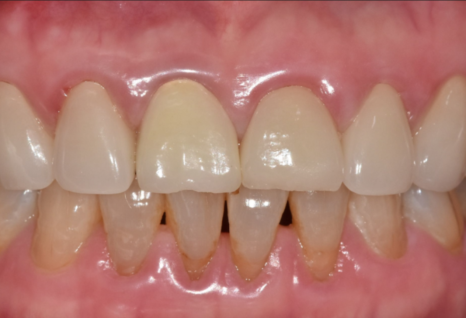

드디어 완성된 모습입니다.

어떤 게 임플란트인지 한눈에 찾기 어려우시죠?

241101

색상은 물론이고 모양까지

주변 치아와 참 잘 어우러져서

환자분도 저도 무척 만족스러웠던 사례였습니다.^^